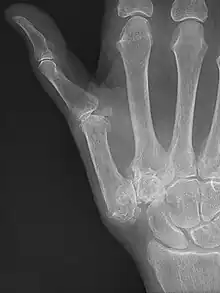

Diagnosis

TMC OA is diagnosed based on symptoms and signs.[8] Radiographs can confirm the diagnosis and the severity of TMC OA. Other diagnoses in this region include scaphotrapezial trapezoid arthritis and first dorsal compartment tendinopathy (De Quervain syndrome) although these are usually easy to distinguish.

Classification

TMC OA severity was classified by Eaton and Littler which can be simplified as follows:[21][22]

Stage 1:

Stage 2:

Stage 3:

- Slight joint space narrowing

- Narrow joint space

- Concomitant scaphotrapezial arthritis

A simpler classification is no arthritis, some arthritis, and severe arthritis.[23] This simpler classification system omits the potentially contradictory details of the Eaton/Littler classification and keeps scaphotrapezial arthrosis separate.